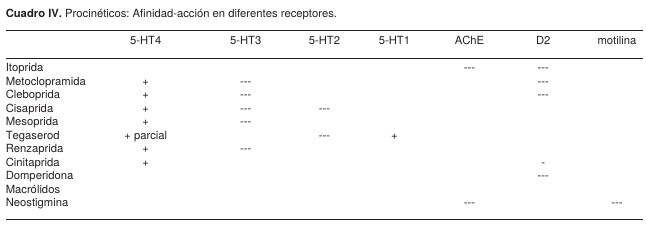

TRATAMIENTO

El tratamiento médico general del SO comprende diversas alternativas terapéuticas (Figura 3), desde medidas generales poco invasivas hasta la utilización de la descompresión colónica por colonoscopia y cirugía. Frecuentemente se inicia con ayuno (reposo intestinal), sonda nasogástrica y rectal, enemas evacuantes, cambios posturales, tratamiento de la enfermedad de origen, reposición hidroelectrolítica y supresión de drogas potencialmente implicadas en el desarrollo del síndrome.9,10-15 El tratamiento farmacológico más recomendado actualmente en SO es para corregir el desequilibrio del sistema autónomo de la motilidad colónica,5,10-12,16,19 basados en este hecho, se han utilizado actualmente la cinitaprida, la mesaprida y la itoprida,34 por su acción procinética sobre el colon, y su potente acción selectiva sobre los receptores 5-HT4, 5-HT2 y D2 produciendo liberación de acetilcolina en los plexos mientéricos (Cuadro IV).